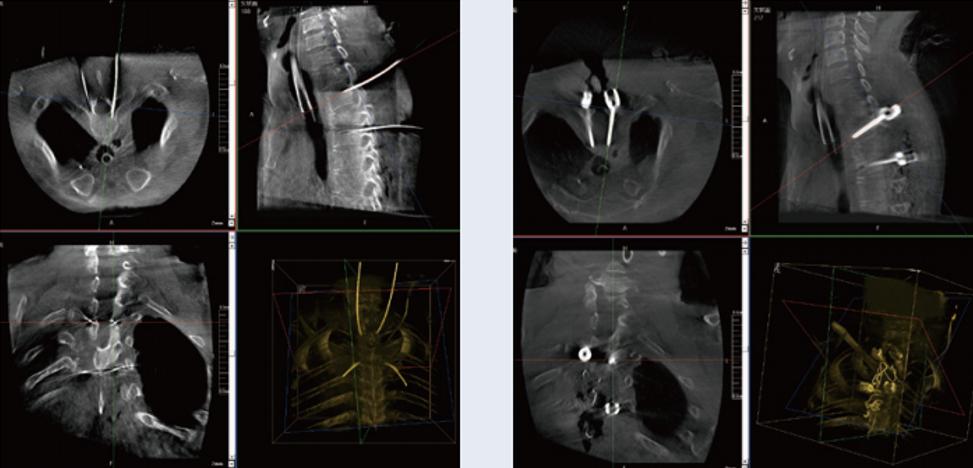

螺釘規劃后的圖像

植入螺釘后的圖像

術中三維C臂與骨科導航機器人配合應用,實現準確定位,確保了手術安全、高效完成。術后二維、三維影像顯示手術效果良好,達到預期目的。

普愛醫療三維C臂提供了高質量的術中實時三維圖像數據,保障了骨科導航機器人手術的準確度和安全性,取得不錯的手術效果。同時,三維C臂特有的斷層成像,能幫助醫生在術中非常直觀地判斷螺釘植入的準確度。